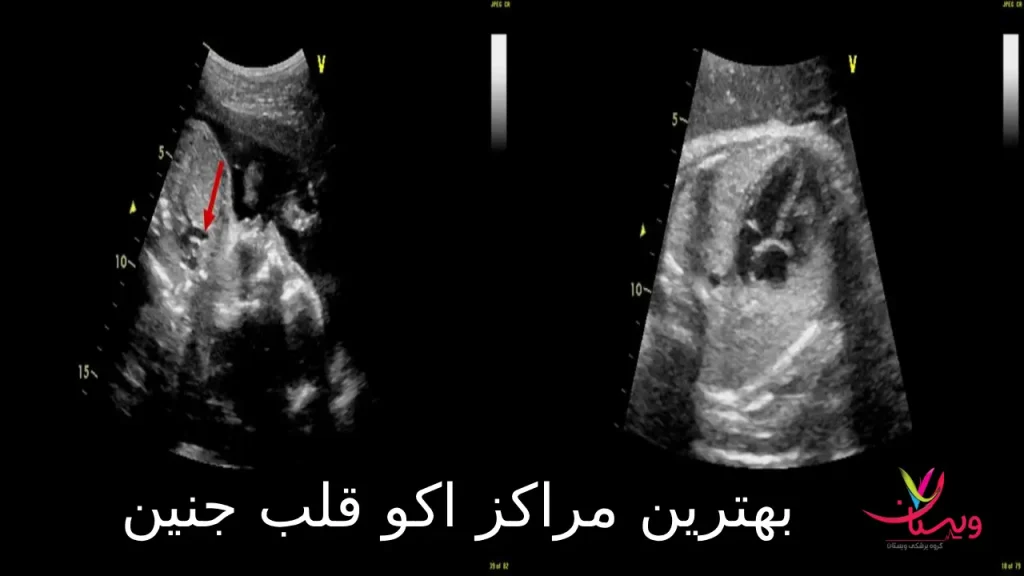

به همین دلیل، بسیاری از والدین به دنبال بهترین مراکز اکو قلب جنین هستند تا این بررسی حساس و حیاتی را در یک محیط تخصصی و مطمئن انجام دهند. اکو قلب جنین (Fetal Echocardiography) یک سونوگرافی پیشرفته است که ساختار و عملکرد قلب جنین را بهطور دقیق بررسی میکند و نقش مهمی در شناسایی مشکلات احتمالی ایفا دارد.

در این مقاله قصد داریم به شما کمک کنیم معیارهای انتخاب یک مرکز معتبر را بشناسید، با برخی از بهترین مراکز اکو قلب جنین در ایران آشنا شوید، و در نهایت دریابید چرا کلینیک چندتخصصی ویستان میتواند یکی از انتخابهای برتر در این زمینه باشد.